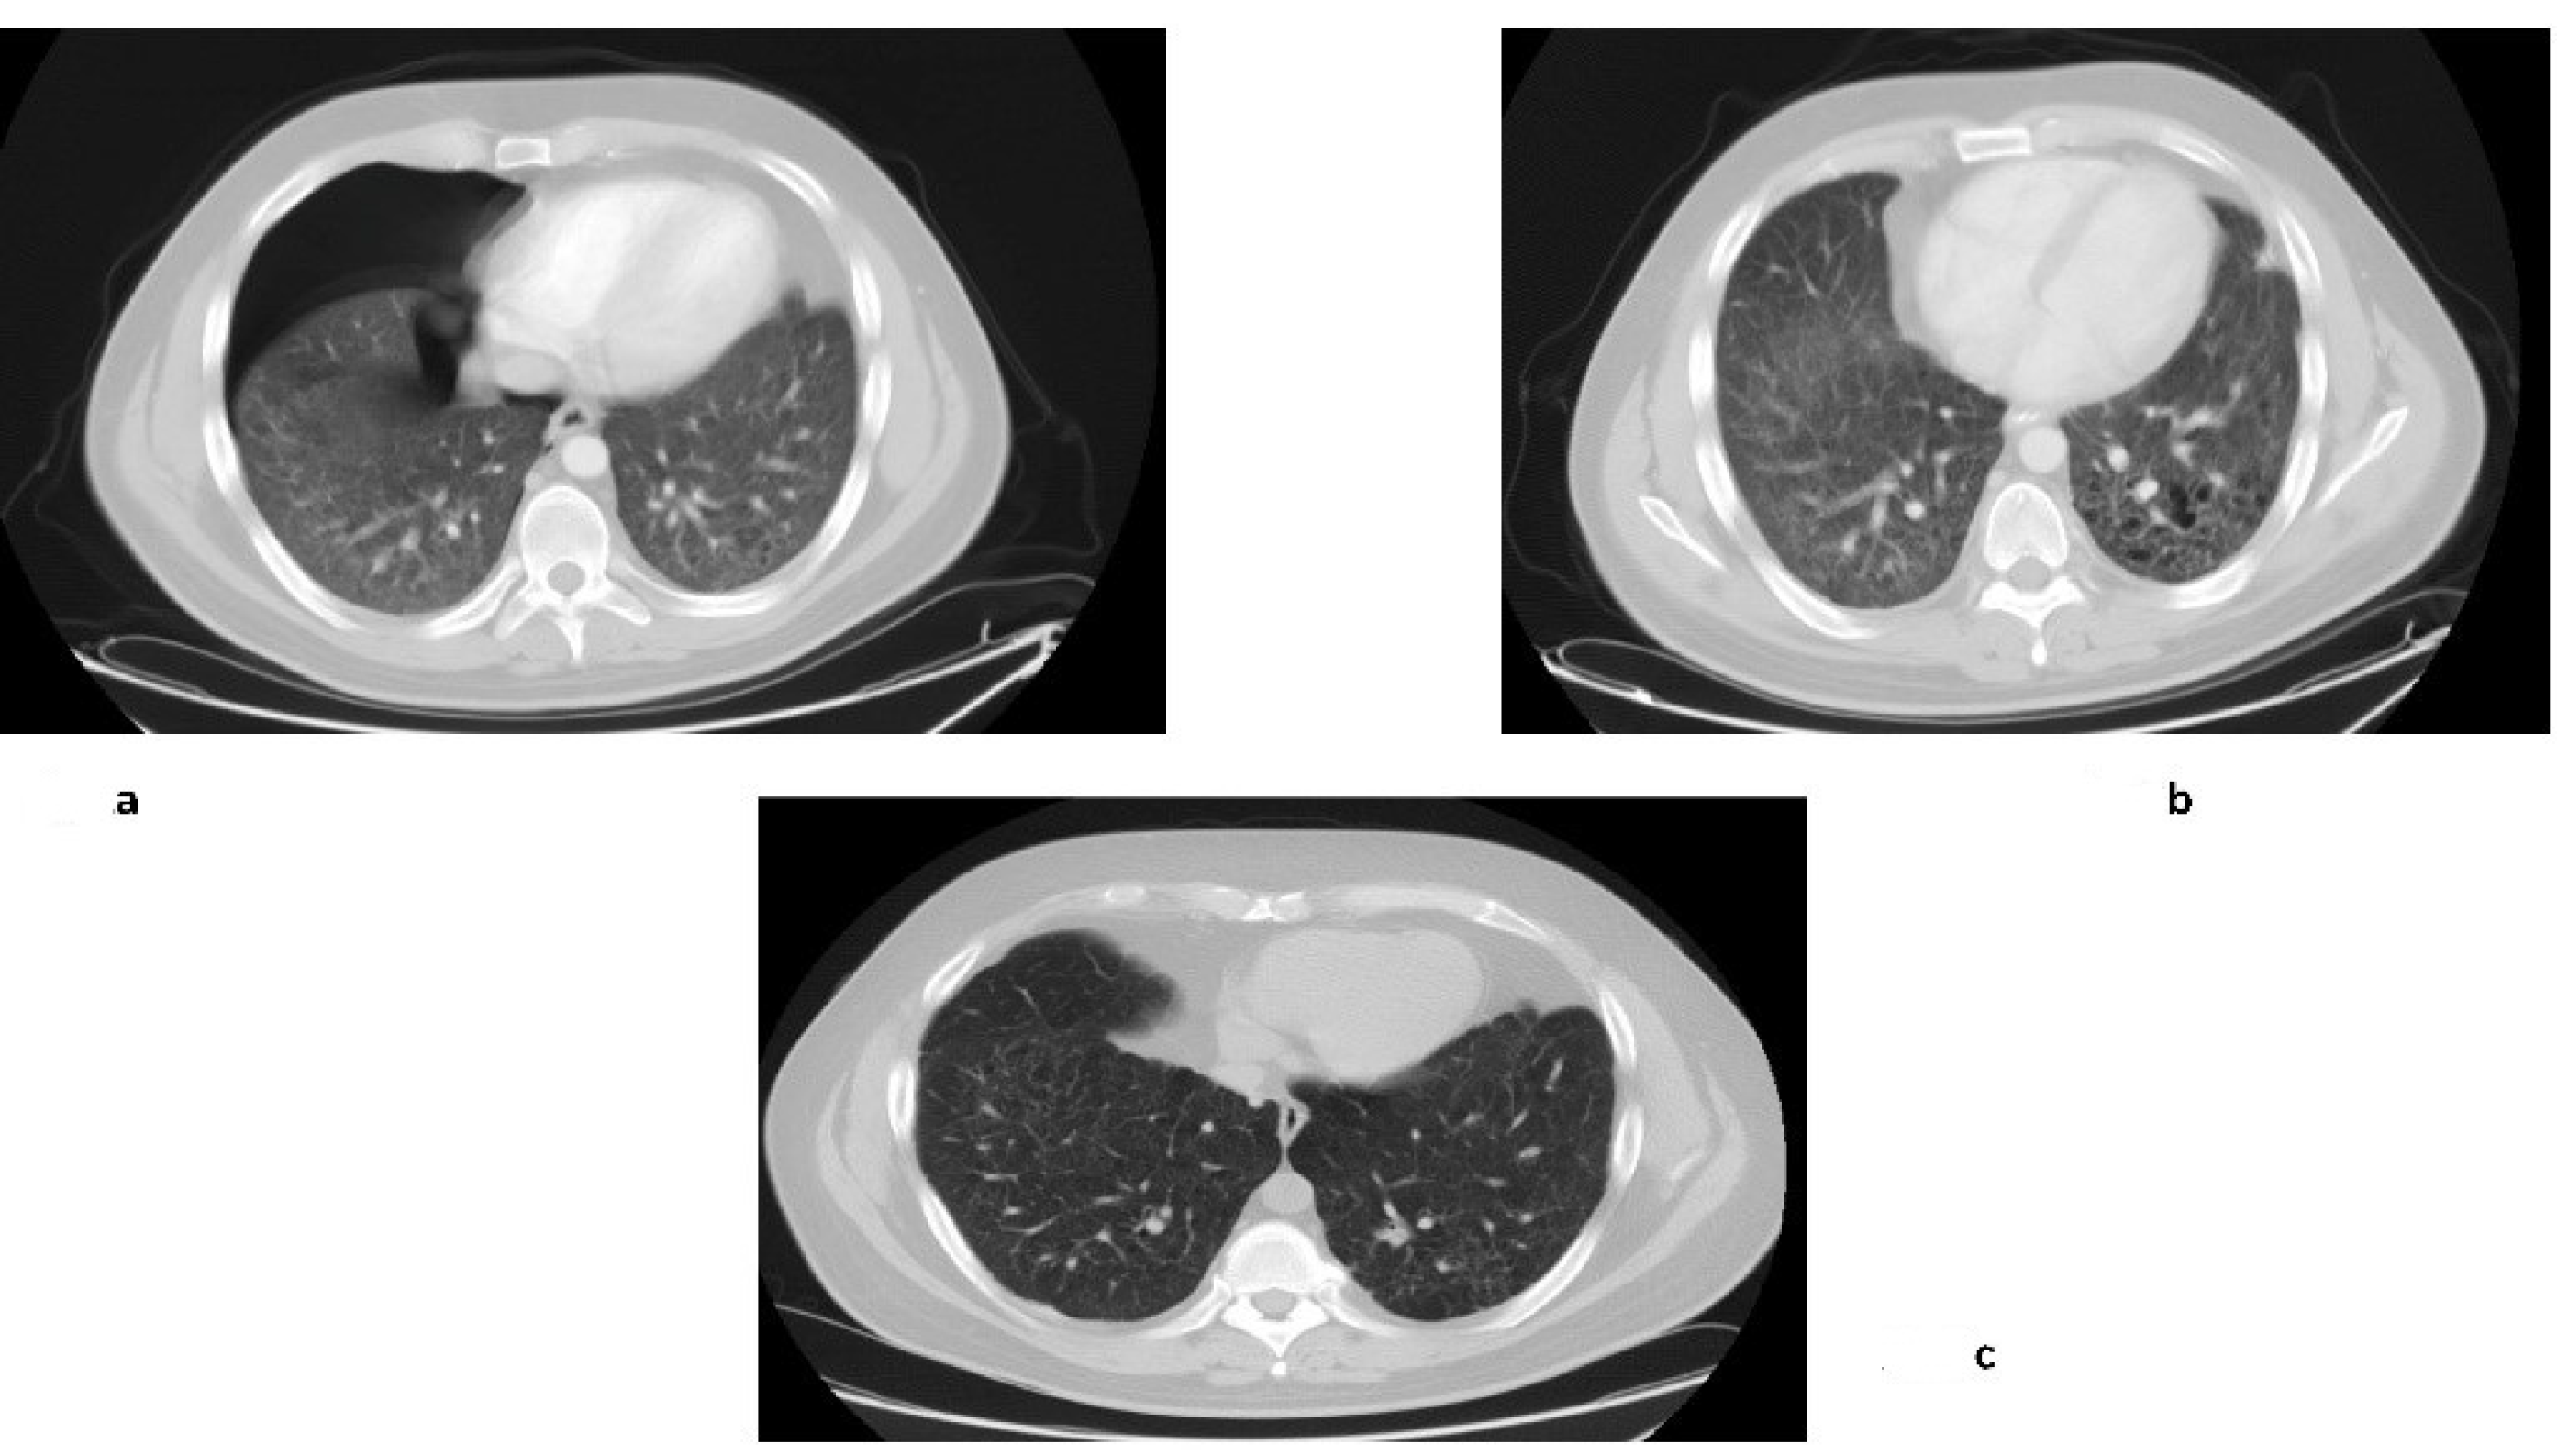

| 1 | 25 | M | Cough | Lung, multi-bone | CR Heart–lung transplantation avoided (10 yrs) | Vbl + Pdn | - | 12 years + 1 month | A |

| 2 | 46 | F | Cough, weight loss | Lung | PR (10 yrs) | Vbl + Pdn | - | 11 years + 6 months | A |

| 3 | 41 | F | Cough, headache, memory disturbances | Lung, brain, multi-bone | Brain and bone CR/lung PR (9 yrs) | Vbl + Pdn Cladribine Indomethacin | Cladribine Vbl + Pdn | 8 years + 6 months | A |